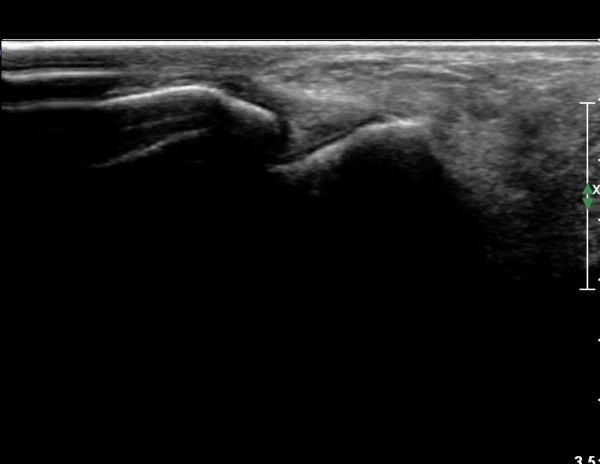

Àü°ÅºñÀÎ´ë ºÎÇϰ˻翡¼­ ÀδëÆÄ¿­ ºÎÀ§°¡ ¹ú¾îÁö°í °Å°ñÀÌ ¾ÕÀ¸·Î ´Ü°ÜÁö´Â ¼Ò°ßÀ» º¸ÀÓ(»çÁø 3, 4, ÷ºÎ µ¿¿µ»ó).